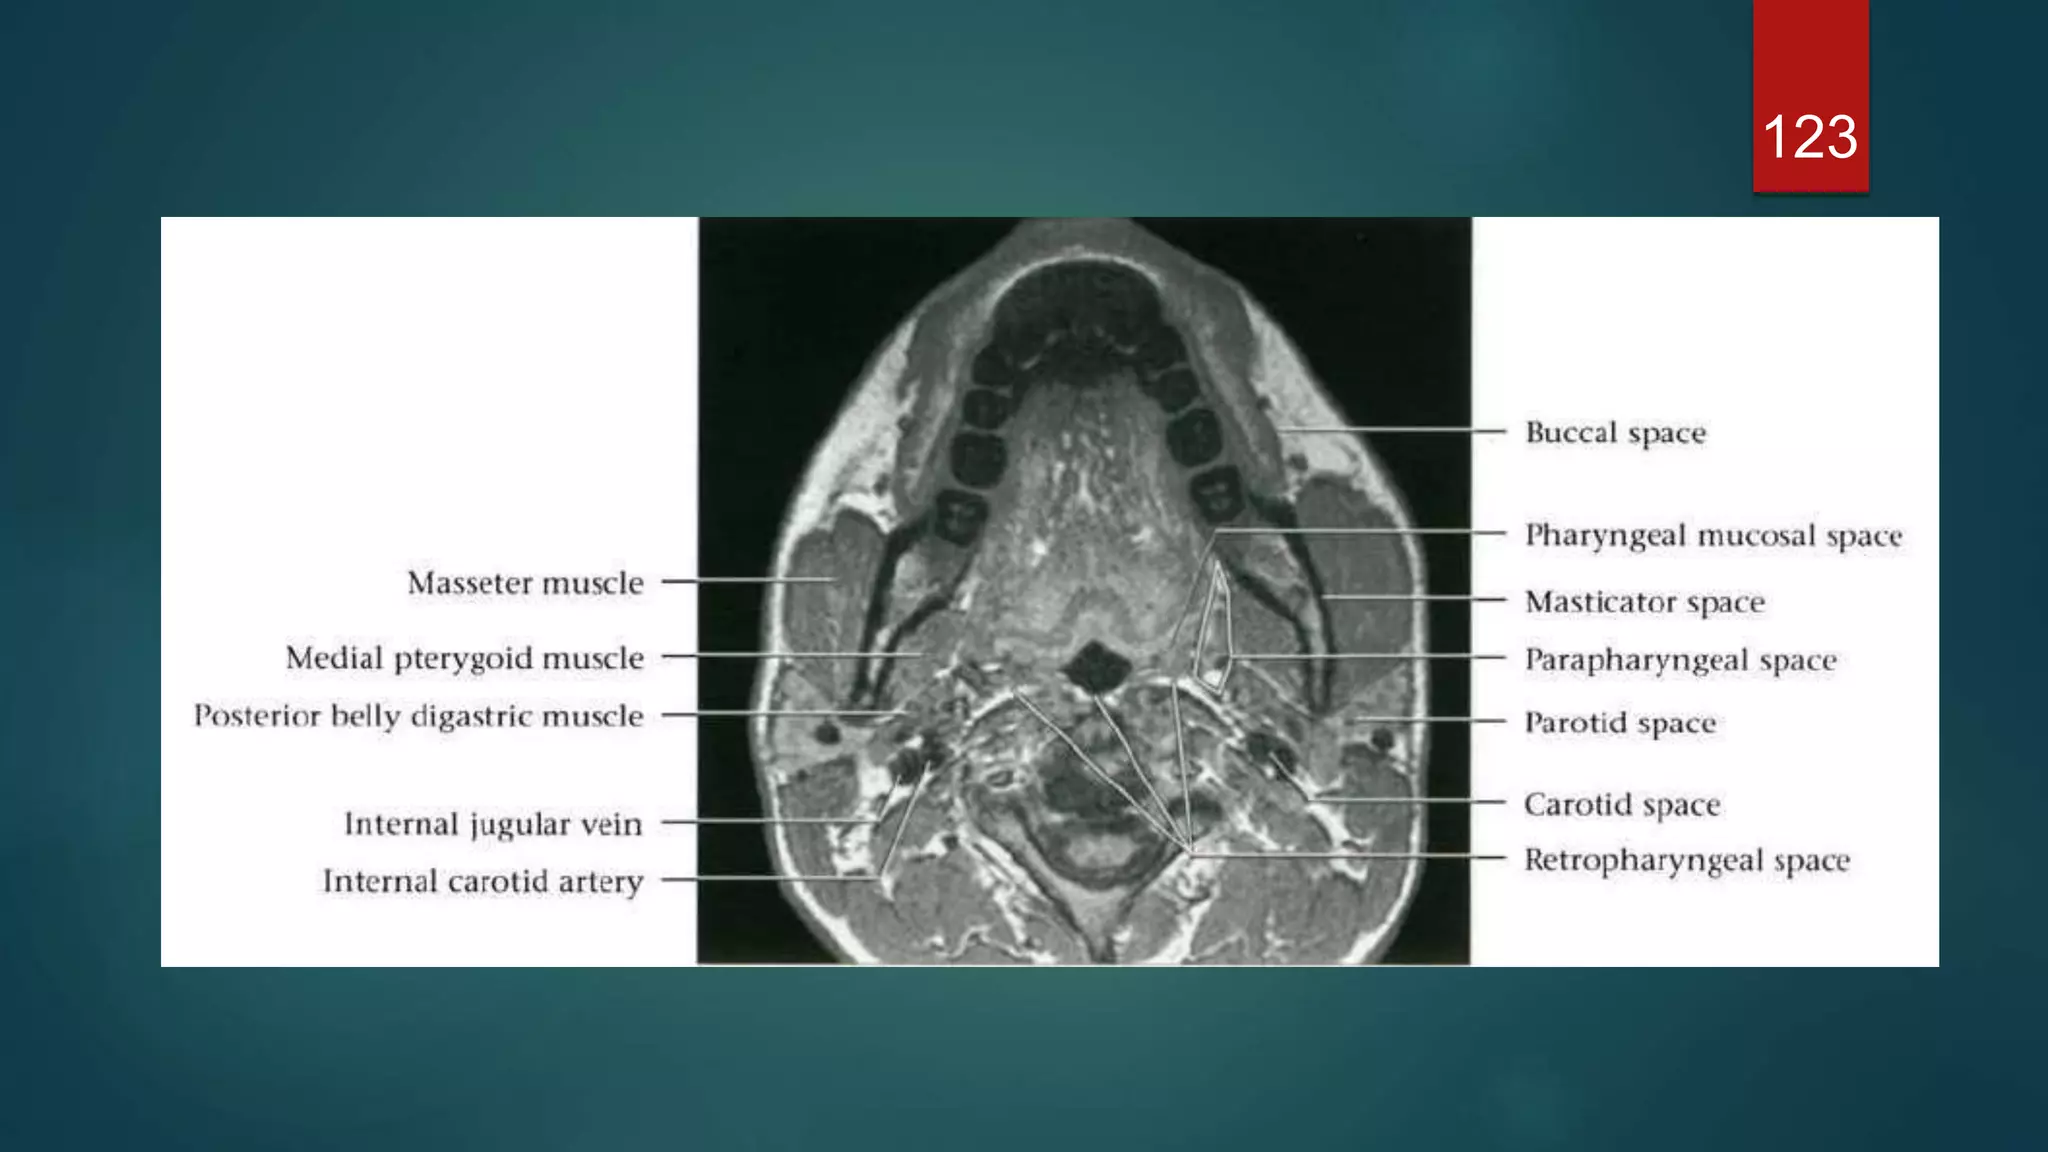

121

122

123